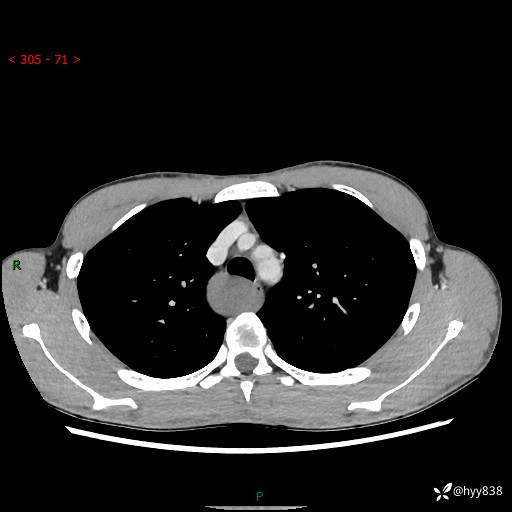

年轻男性,发现后纵隔占位1周余。征象简单,难在定位---结果公布~

现病史:患者于1周前体检行检查发现后纵隔占位,患者平素无明显咳嗽咳痰,无心慌、胸闷、胸痛、呼吸困难、低热、盗汗,无头痛、头晕,无腹痛、腹胀等不适。现患者欲求进一步治疗,遂来我院就诊,以“纵隔占位”收入我科。 患者自起病以来,精神可,睡眠可,饮食可,大小便正常,体重无明显改变。

胸部CT平扫+增强